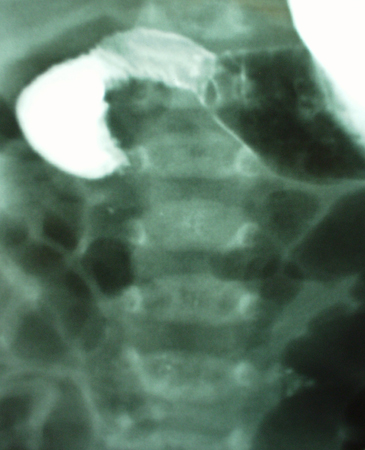

- abdominal x-ray:

dilated small bowel loops, air-fluid levels throughout abdomen

gaseous distension of large bowel; volvulus suggested by kidney-bean-shape bowel loop